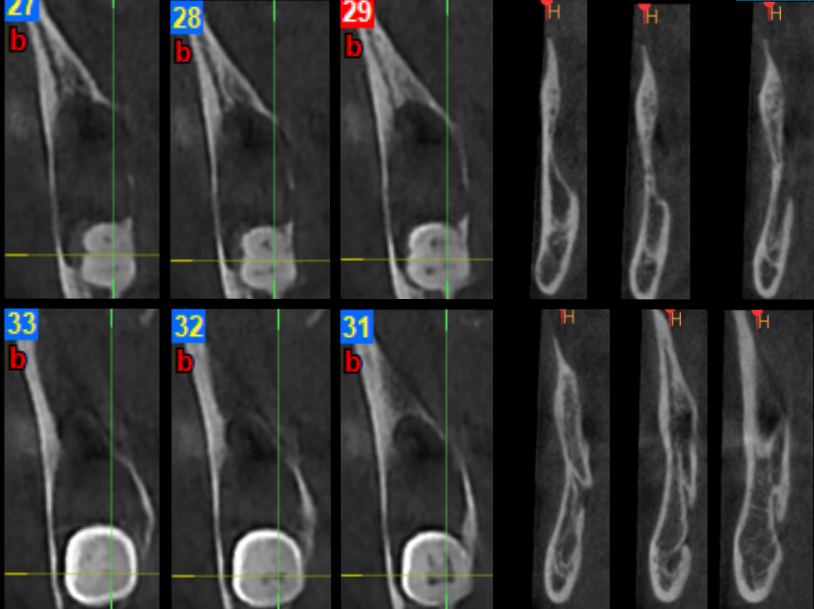

Na kolejne badanie kontrolne pacjentka zgłosiła się po 1,5 roku od zabiegu. Nie zgłaszała żadnych dolegliwości bólowych. W badaniu klinicznym stwierdzono ciągłość blaszki zbitej gałęzi, trzonu i kąta żuchwy po stronie prawej. Wykonano badanie CBCT, które wykazało prawidłowe utkanie tkanki kostnej w obrębie gałęzi, kąta i trzonu żuchwy (ryc. 4 i 5).

Ryc. 4. Badanie CBCT, rekonstrukcje pseudotrójwymiarowe: po stronie lewej badanie przedzabiegowe (listopad 2020), po stronie prawej – badanie kontrolne po 1,5 roku od zabiegu (maj 2022).

Ryc. 5. Rekonstrukcje transsektalne: po stronie lewej badanie CBCT przedzabiegowe (listopad 2020), po stronie prawej badanie kontrolne po 1,5 roku od zabiegu (maj 2022) – pełne wygojenie kości.